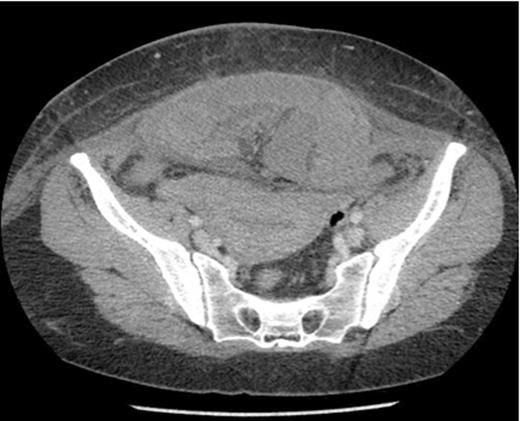

Axial section showing dilated loops of small bowel and a segment of small bowel adherent to the anterior abdominal wall.

The next day she became pyrexial (38°C) and tachycardic (103 bpm). Examination revealed a tender abdomen, with guarding and absent bowel sounds. Her neutrophilic leukcytosis increased from 13 to 27 and CRP increased to 159. She was commenced on gentamicin and a CT abdomen/pelvis was ordered. Radiology reported a high-grade acute SBO secondary to herniation of segment of small bowel into anterior abdominal wall defect. A laparotomy was performed and revealed a segment of strangulated small bowel lying above the rectus muscles and trapped beneath the intact rectus sheath. 34cm of necrotic small bowel was resected and an end to end anastomosis was fashioned. The patient made a good post-operative recovery and was discharged 9 days later.